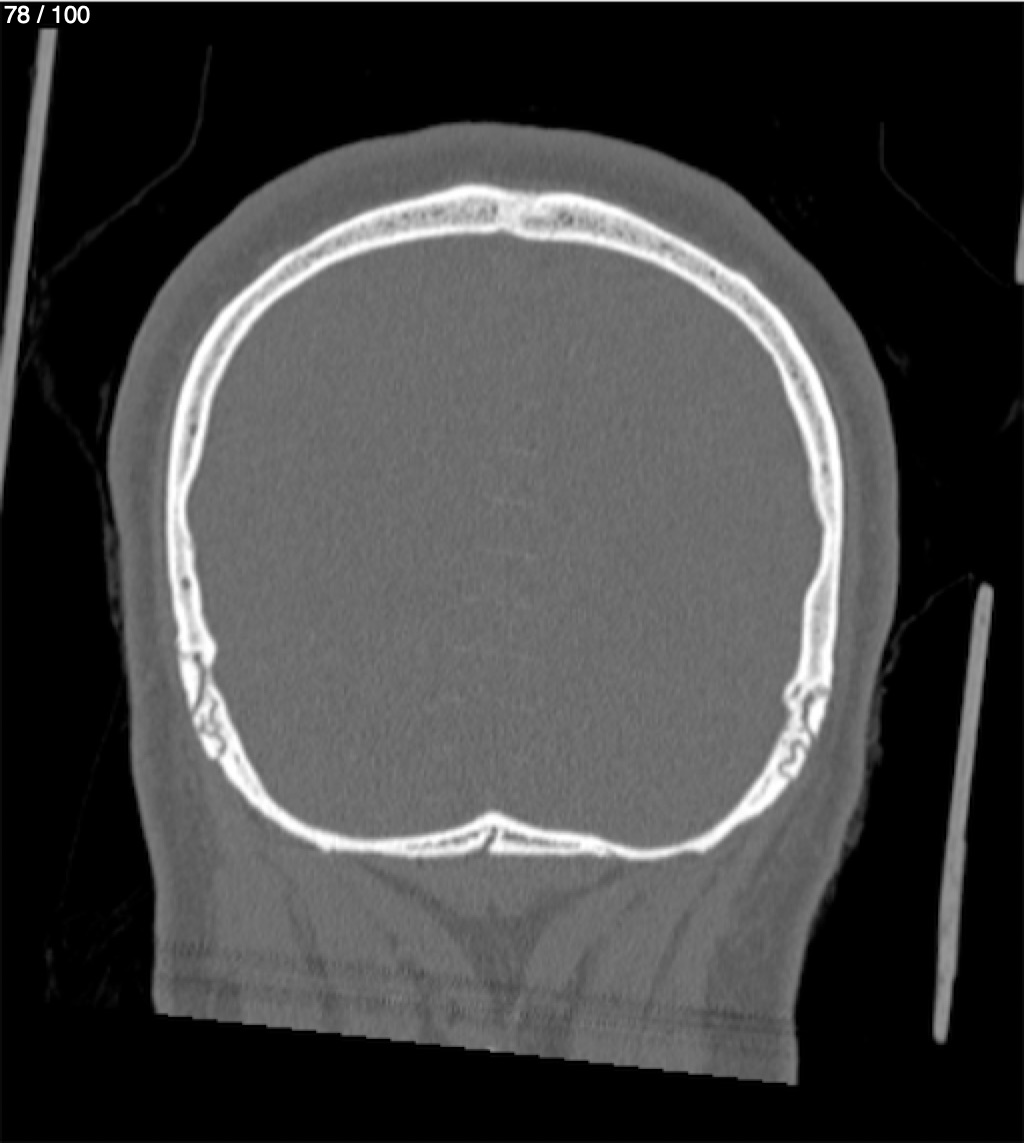

Reybet Garcia Fuentes 30A - T.C Craneo